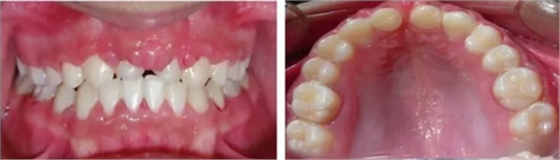

車禍后,一名10歲男孩被送往Shariati醫(yī)院急診科。診斷出上頜中切牙的脫落和側(cè)切牙的嵌入(圖1)。脫落的中切牙丟失了,沒(méi)有進(jìn)行再植。全景片示除第二磨牙外的恒牙列(圖2)。

圖1. 初診口內(nèi)照